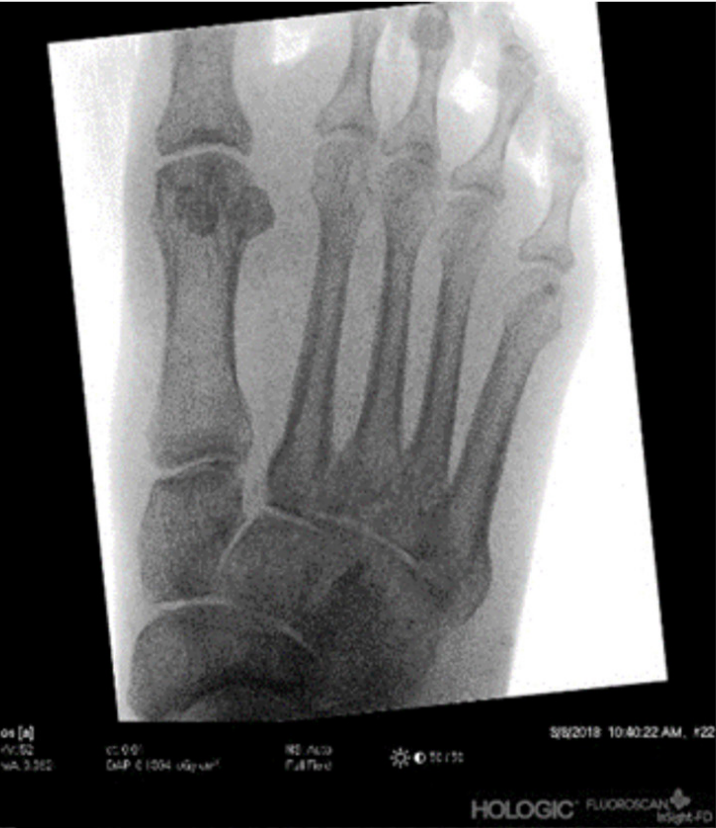

站立位足部正位X线片显示,与健侧足部相比,Lisfranc关节分离超过2mm(测量内侧楔骨外侧缘与第二跖骨基底内侧缘之间的距离);

▲图示麻醉状态下,通过术中透视观察到Lisfranc关节分离情况。